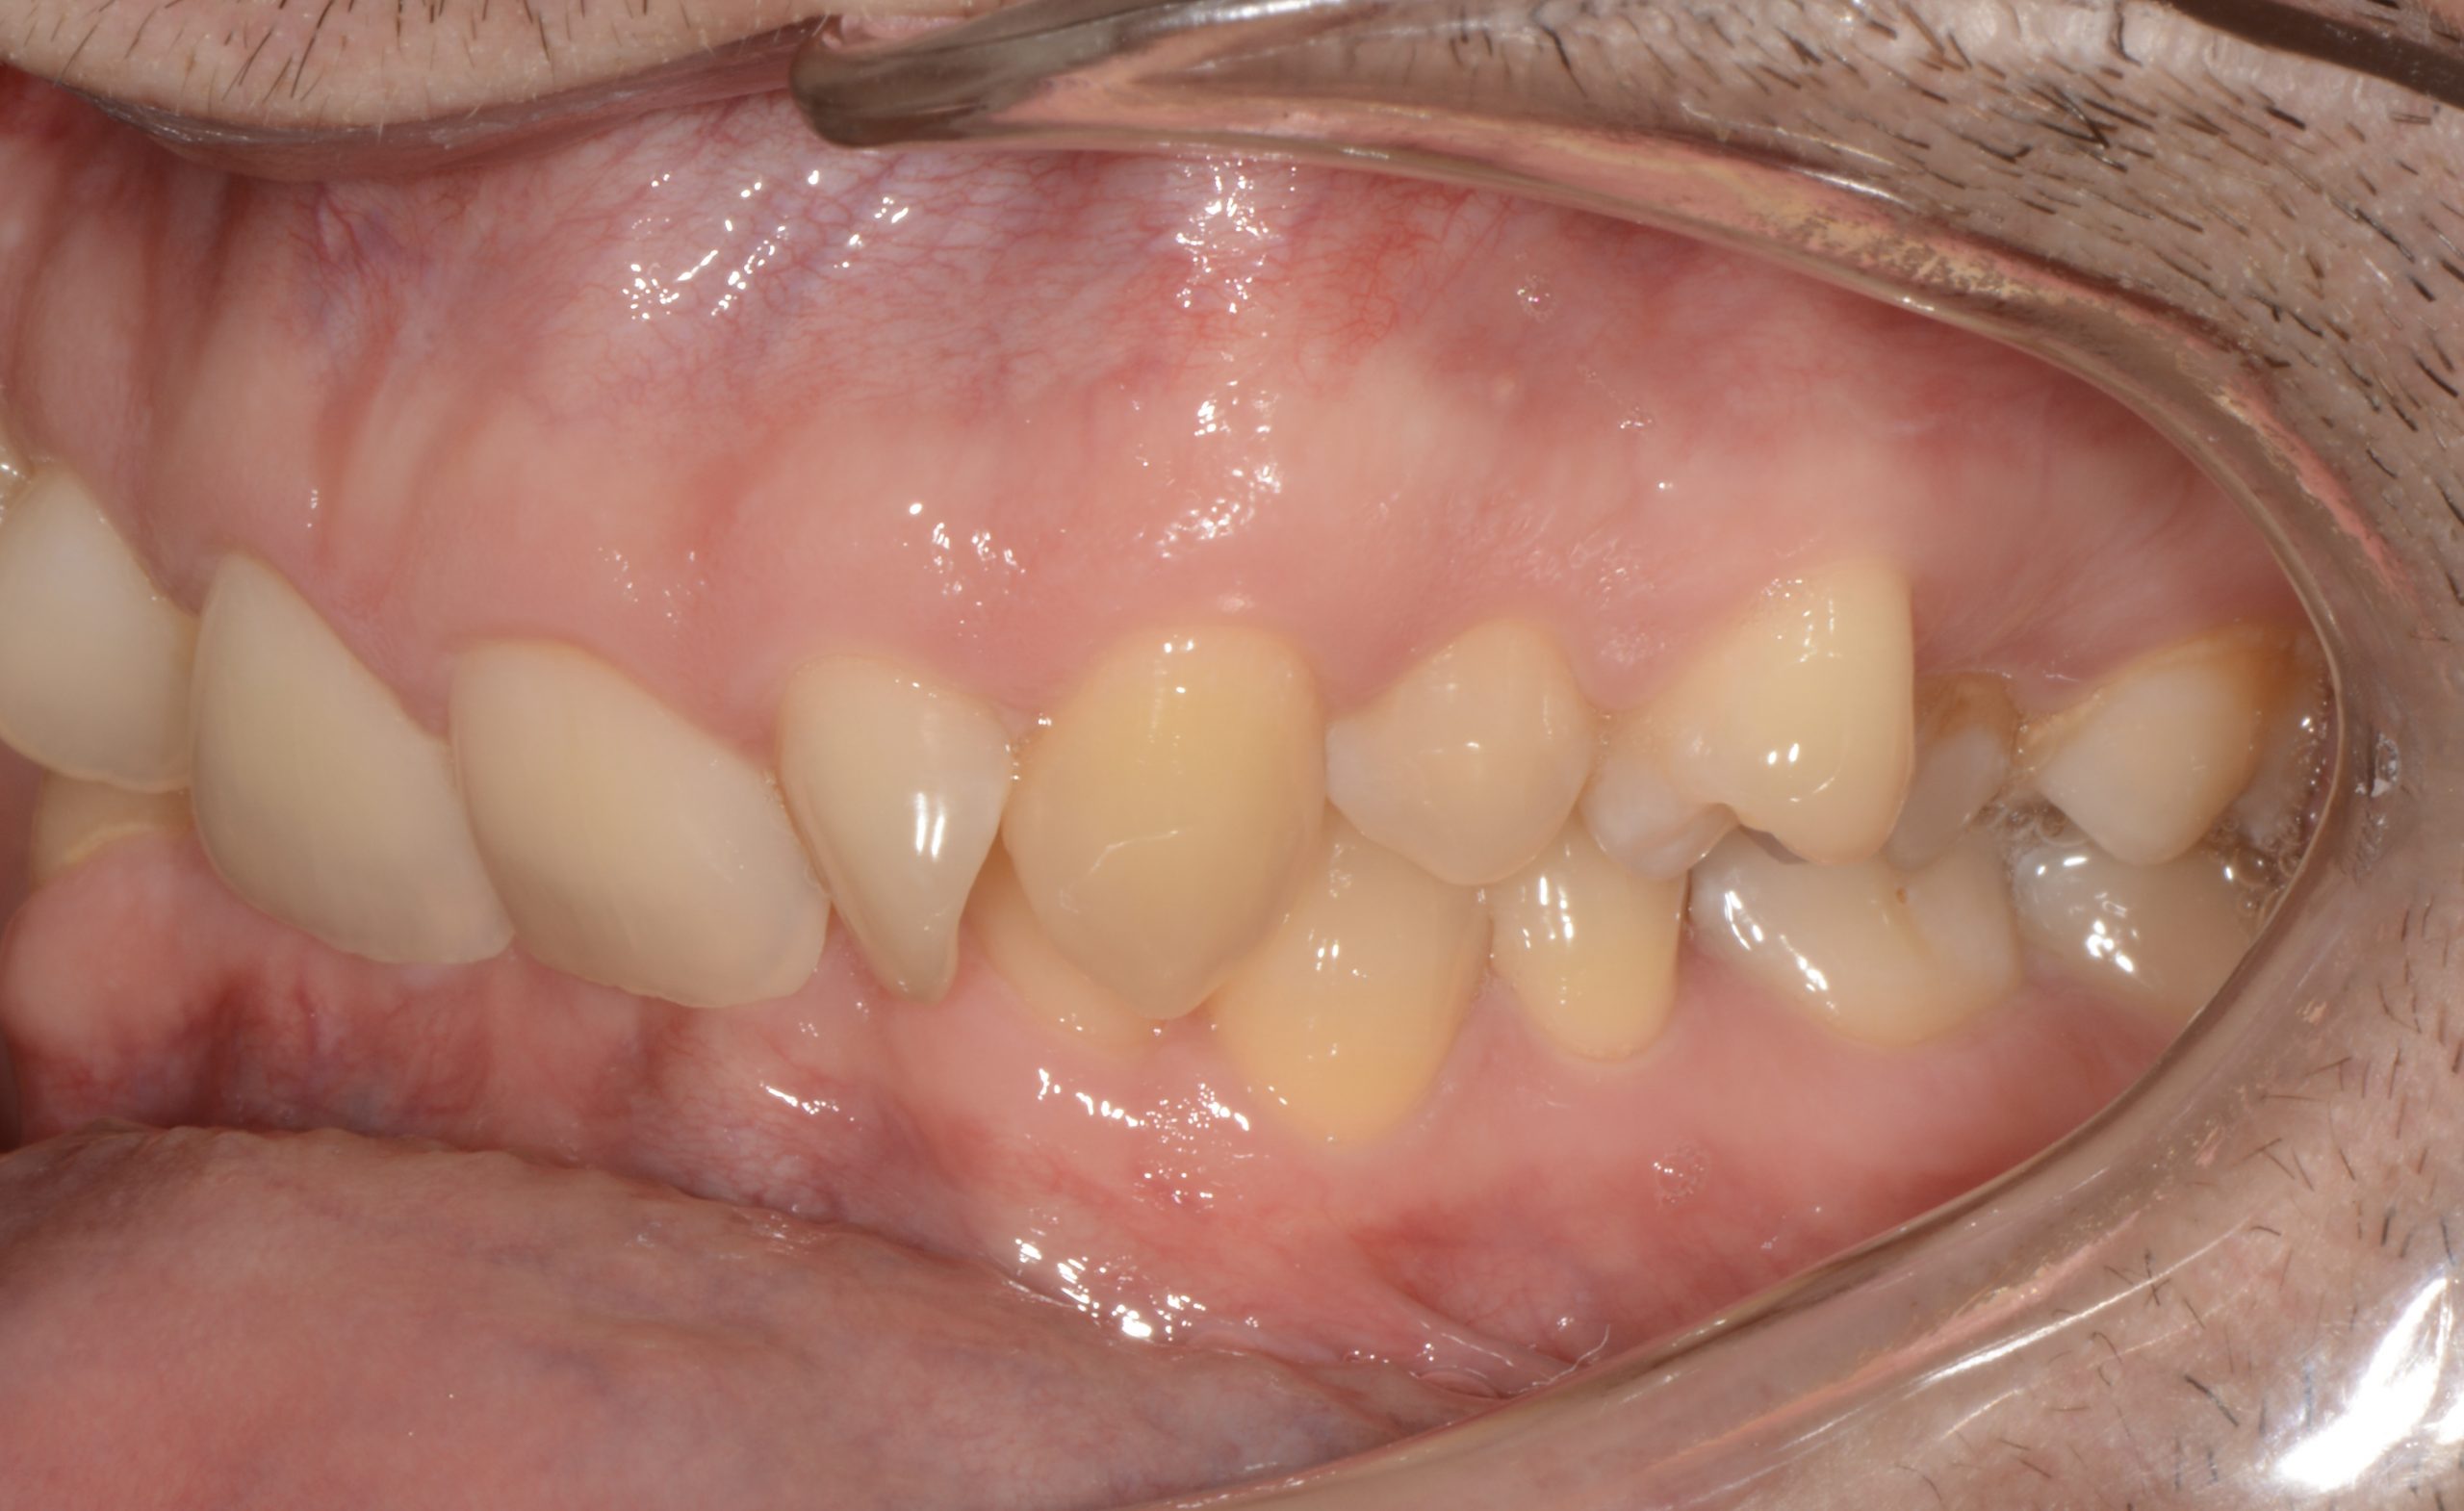

Az elmúlt évekből rengeteg szakmai referenciát tudnánk bemutatni, amelyek különböző fogszabályozási problémákat oldottak meg. Válogatva a több száz esetből, ezen az oldalon olyan képeket, információkat igyekeztünk bemutatni, amelyeknek a segítségével a jövőbeni pácienseinknek azt tudjuk üzenni: A Te fogsorod is lehet gyönyörű!

(Képeket a Pácienseink külön írásos beleegyezésével mutatjuk be!)